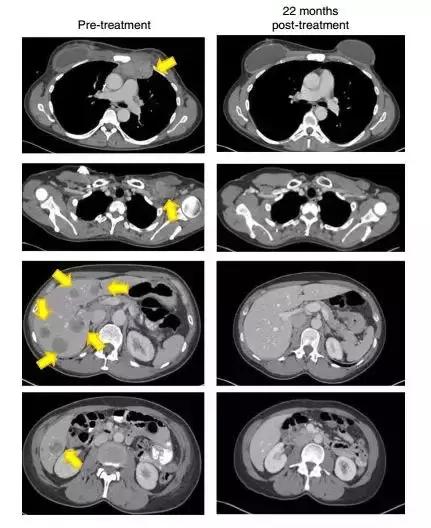

晚期乳腺癌接受治疗22个月后,这名患者的肿瘤(黄色箭头)消失得无影无踪

(图片来源:《Nature Medicine》)